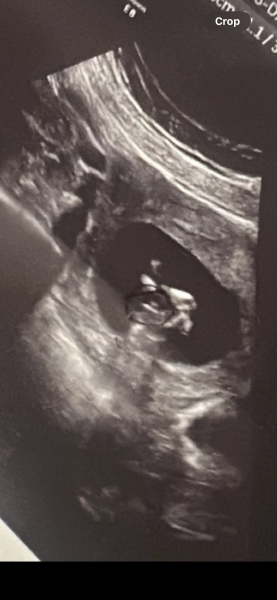

Hi, I went for an early gender scan at 13 weeks (I know most places don’t do this 🤦🏽‍♀️) but I’m confused by the scan that I was given, I can see why they said boy but when I’m looking I don’t see the genitals are actually connected to the body? Am I just being stupid? Haha I will attach the picture I received.

Sorry OP I’m a sonographer and I can’t actually figure out the anatomy in that photograph.

Hi I’ve only just seen your reply sorry! Can confirm baby is definitely a boy 🤣I don’t know how they could tell from that but amazing! 😂😂